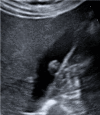

Gallbladder polyps are protuberances of the gallbladder wall projecting into the lumen. They are usually incidentally found during abdominal sonography or diagnosed on histopathology of a surgery specimen, with an estimated prevalence of up to 9.5% of patients. Gallbladder polyps are not mobile and do not demonstrate posterior acoustic shadowing; they may be sessile or pedunculated. Gallbladder polyps may be divided into pseudopolyps and true polyps. Pseudopolyps are benign and include cholesterolosis, cholesterinic polyps, inflammatory polyps, and localised adenomyomatosis. True gallbladder polyps can be benign or malignant. Benign polyps are most commonly adenomas, while malignant polyps are adenocarcinomas and metastases. There are also rare types of benign and malignant true gallbladder polyps, including mesenchymal tumours and lymphomas. Ultrasound is the first-choice imaging method for the diagnosis of gallbladder polyps, representing an indispensable tool for ensuring appropriate management. It enables limitation of secondary level investigations and avoidance of unnecessary cholecystectomies.